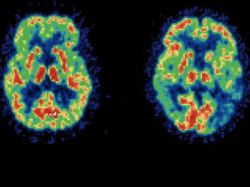

Científicos argentinos descubrieron un mecanismo que provee nuevos datos sobre el funcionamiento de la comunicación entre neuronas, lo que puede aportar vías para la comprensión de enfermedades como el mal de Alzheimer, informó este lunes a Efe la investigadora a cargo del estudio.

Para la investigadora, el estudio da una luz sobre cómo funciona la sinapsis y puede ayudar a crear nuevas vías para entender las enfermedades de este tipo, entre las que se encuentra el mal de Alzheimer y la esclerosis.

Durante el trabajo, publicado en la revista The Journal of Cell Biology, los científicos analizaron en roedores neuronas del hipocampo, la región del cerebro asociada con los aspectos cognitivos.